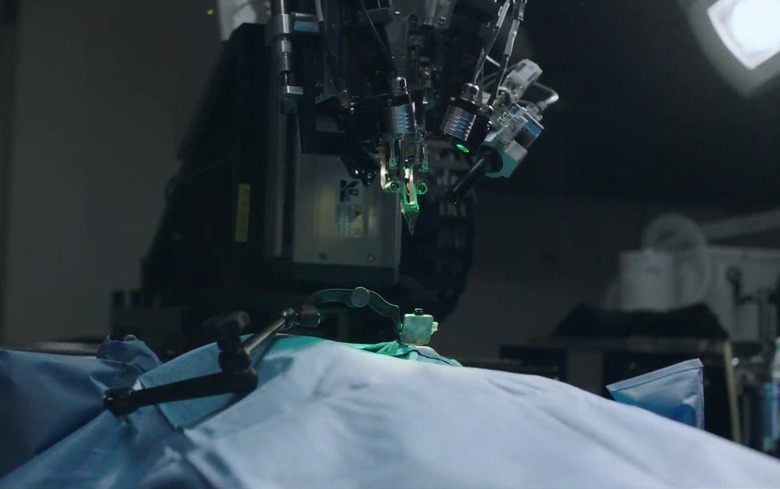

A 'sewing machine-like' robot implants threads directly into the brain.

While we waited for Neuralink to present the progress it's made over the last couple of years in brain-computer interface technology, the New York Times and Bloomberg published information from an early briefing and it's stuff that's straight out of science fiction. The Elon Musk-backed company claims its "sewing machine-like" robot will be able to implant threads deep into a human brain.

Neuralink president Max Hodak went on to explain why it's embedding sensors directly into the brain, near but not in neurons. Simply, it's the only way to send and receive the information necessary, from "spikes" of activity. A neurosurgeon is also part of the presentation, showing off some videos of the implantation technology, and how its robot can install thousands of wires directly into the brain while avoiding tissue damage and bleeding. Eventually, they'd like to do it without shaving the patient's head, although he acknowledged that the first operations will be more like current deep brain implants.